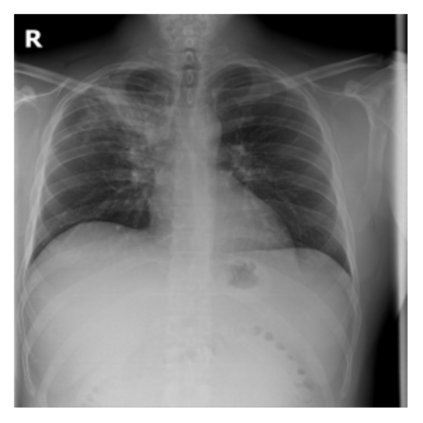

The evaluation of infectious disease processes on radiologic images is an important and challenging task in medical image analysis. Pulmonary infections can often be best imaged and evaluated through computed tomography (CT) scans, which are often not available in low-resource environments and difficult to obtain for critically ill patients. On the other hand, X-ray, a different type of imaging procedure, is inexpensive, often available at the bedside and more widely available, but offers a simpler, two dimensional image. We show that by relying on a model that learns to generate CT images from X-rays synthetically, we can improve the automatic disease classification accuracy and provide clinicians with a different look at the pulmonary disease process. Specifically, we investigate Tuberculosis (TB), a deadly bacterial infectious disease that predominantly affects the lungs, but also other organ systems. We show that relying on synthetically generated CT improves TB identification by 7.50% and distinguishes TB properties up to 12.16% better than the X-ray baseline.

翻译:放射图像中的传染病过程评估是医学图像分析中一项重要而具有挑战性的任务。 肺感染通常可以通过计算成的XX扫描进行最佳的成像和评估,这些扫描往往在资源贫乏的环境中得不到,而且病人很难获得。另一方面,X光是一种不同类型的成像程序,价格低廉,常常在床边提供,而且可以更广泛地获得,但提供一种更简单、更简单的二维图像。我们表明,通过依靠一种能够学会合成X光生成CT图像的模式,我们可以提高自动疾病分类的准确性,并向临床医生提供对肺病过程的不同看法。具体地说,我们调查结核病,这是一种致命的细菌传染病,主要影响肺部,但也影响其他器官系统。我们表明,依靠人工生成的CT,可以提高7.50%的结核病识别率,并将结核病特性区分为12.16%,比X光基线要好得多。